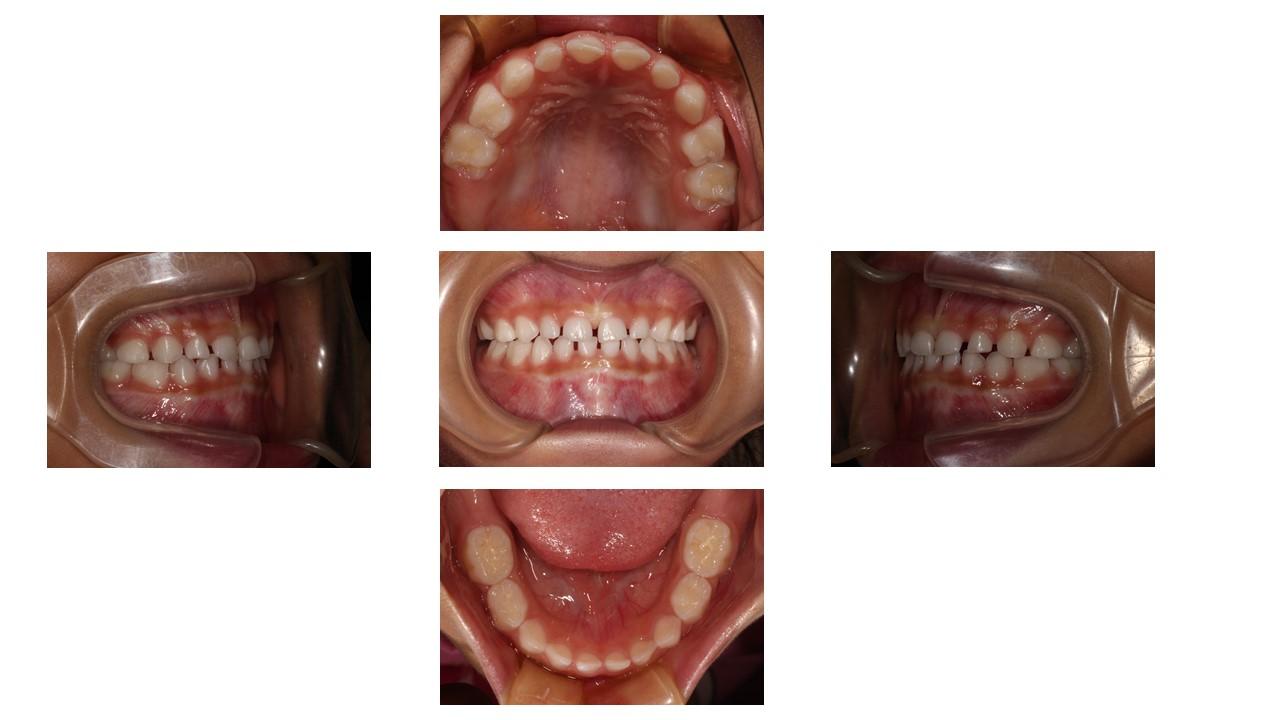

「叢生」は、一般的に「乱ぐい歯(らんぐいば)」「八重歯(やえば)」「ガタガタの歯並び」などと呼ばれる状態で、日本人に非常によく見られる不正咬合(ふせいこうごう:良くない噛み合わせ)です。

<叢生の状態>

顎(あご)の骨の大きさに対して、歯のサイズが大きすぎたり、歯が並ぶスペースが不足していたりするために、歯がデコボコに重なり合って生えている状態を指します。

叢生を治療し、歯並びをきれいに整えることは、毎日の歯磨きを容易にし、虫歯や歯周病を予防するとともに、顎関節や全身の健康を守るための大切な投資となります。